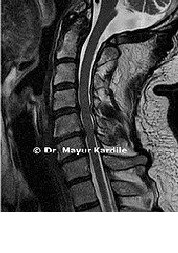

A 51-year-old gentleman complained of pain and weakness in the right arm.

MRI revealed foraminal narrowing and nerve root compression at C4-5, C5-6, C6-7

C4-5, C5-6, C6-7 Anterior cervical discectomy and fusion (ACDF) surgery was done to relieve the pressure on the cervical nerve roots.